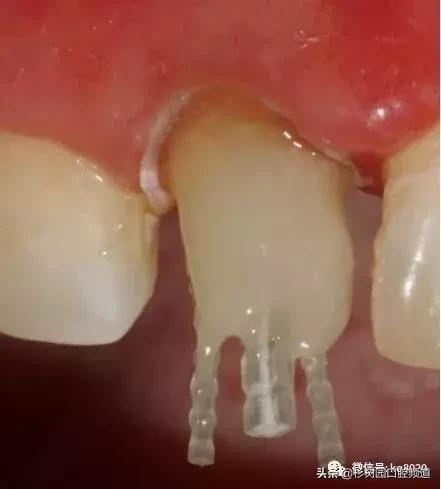

如果后牙需要打多个纤维桩时要检查是否互相妨碍以及就位顺序等。

纤维桩使用数目要根据根管的粗细和牙体缺损范围来设计,可以在主尖周围放置辅尖。后牙一般按照牙体缺损范围来设计,一般2到4个足够了。

推荐将树脂核堆好之后再截断纤维桩,而不是截断后再粘接。如下图: